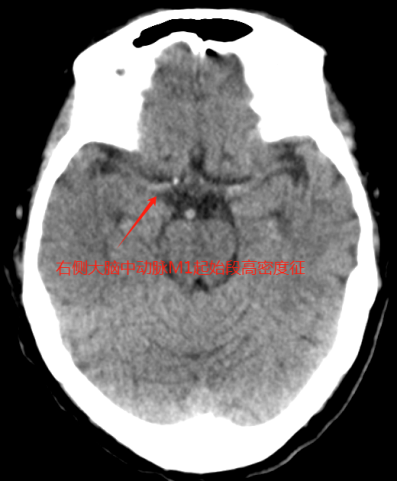

卒中中心值班医师(绿道医师)马上给予指示:收费处绿色通道挂号,院前医师车上完成血液抽取、血糖及心电图检查,并将患者绕行急诊紧急送往CT室进行头颅CT检查。患者心电图显示I、AVL、V5、V6导联ST段明显改变,考虑同时合并急性冠脉综合征,患者存在急性心梗的可能。随即加查肌钙蛋白,同时送检头颅CT平扫+CTA检查。CT检查结果明确了患者右侧大脑中动脉的M1段闭塞,确诊为急性脑梗死。肌钙蛋白检测结果亦回报:12.83ug/ml,结合心电图的表现,确诊为急性非ST段抬高型心肌梗死。

右侧大脑中动脉起始部高密度征